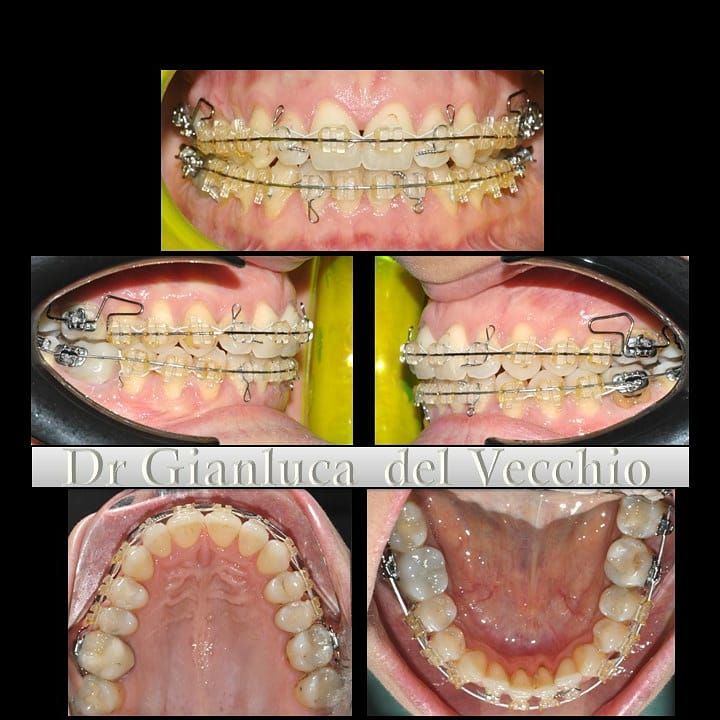

Il dottor Gianluca del Vecchio si occupa esclusivamente di ortognatodonzia, grazie anche alla collaborazione multidisciplinare di una équipe davvero entusiasmante e all’utilizzo di strumenti diagnostici e terapeutici all’avanguardia in ortognatodonzia. Particolare è la sua capacità di condurre i giovani pazienti ad affrontare, nella massima sicurezza emotiva e clinica, qualsiasi eventuale condizione di dolore derivante, ad esempio, da carie o da altre patologie, ma soprattutto di risolvere tutte quelle condizioni di “denti storti”, così spesso causa di disagio psicologico o di fenomeni deprecabili, quale il bullismo.

Il dottore ha acquisito una concezione quanto più pratica e moderna della disciplina e utilizza apparecchietti di diversi colori di tipo mobile e fisso, ma anche terapie sia estetiche che invisibili, fiore all’occhiello di poche realtà in Italia. Per terapie estetiche e invisibili si intendono quelle in grado di spostare i denti, senza che traspaia nulla dalla bocca o con stelline e fili bianchi, esattamente come i denti del paziente.

Ma ancora di più l’équipe è in grado di offrire un servizio davvero unico: la tecnica dei retainer attivi. Questa consiste in fili o bottoni che si incollano dietro i denti e che, quindi, nascondono completamente la terapia. Questo tipo di prestazioni aiuta a superare la grande difficoltà psicologica, che spesso si insinua anche negli adulti, di dover spostare i propri denti per un sorriso perfetto: si consideri che tale difficoltà non viene affrontata, il più delle volte, proprio per l’imbarazzo che una apparecchiatura ortodontica genera in chi la usa. Queste tecniche, insieme alle mascherine invisalign invisibili di cui è provider ufficiale e agli attacchi in ceramica, sono tutte quotidianamente utilizzate presso i nostri reparti, in cui è possibile associarle in un discorso multidisciplinare a tutte le altre esigenze della odontoiatria classica.